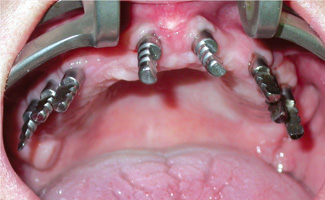

La prima fase chirurgica ha portato all’inserimento di 8 impianti di cui 6 da 3,3 mm di diametro nei settori laterali e 2 da 4,1 mm nei settori anteriori (figg. 4-6).

- Fig. 4

- Fig. 5

- Fig. 6